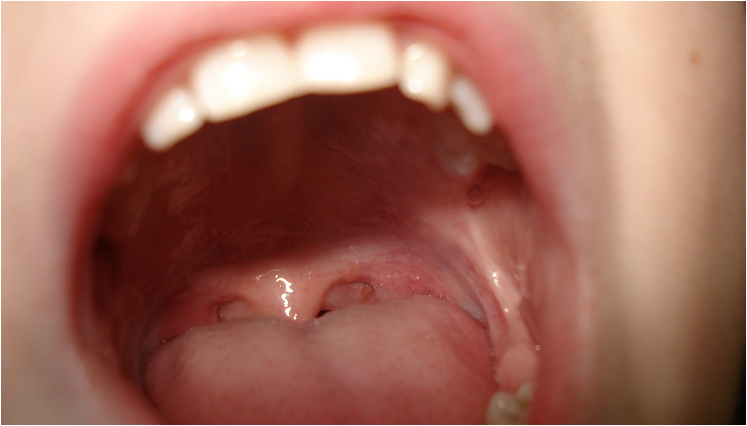

입천장이 붓는 현상은 불편함을 초래하며, 다양한 원인에 의해 발생할 수 있습니다. 이번 포스팅에서는 입천장이 붓는 주요 원인과 이를 치료하는 방법에 대해 알아보겠습니다.

입안의 세균, 바이러스 또는 곰팡이 감염으로 인해 입천장이 부을 수 있습니다. 구강 칸디다증(구강 곰팡이 감염)은 입천장이 붓는 흔한 원인 중 하나입니다.

입천장에 궤양이 생기면 통증과 함께 부종이 발생할 수 있습니다. 구강 궤양은 스트레스, 면역력 저하, 영양 결핍 등의 원인으로 발생할 수 있습니다.

뜨거운 음식이나 음료를 섭취하거나 날카로운 물체에 입천장이 찔리면 부종이 생길 수 있습니다. 외상으로 인한 부종은 통증과 함께 나타날 수 있습니다.

드물지만 입천장이 붓는 원인으로 구강암이 있을 수 있습니다. 지속적인 부종과 함께 통증, 출혈, 덩어리 등이 나타난다면 전문의의 진료가 필요합니다.